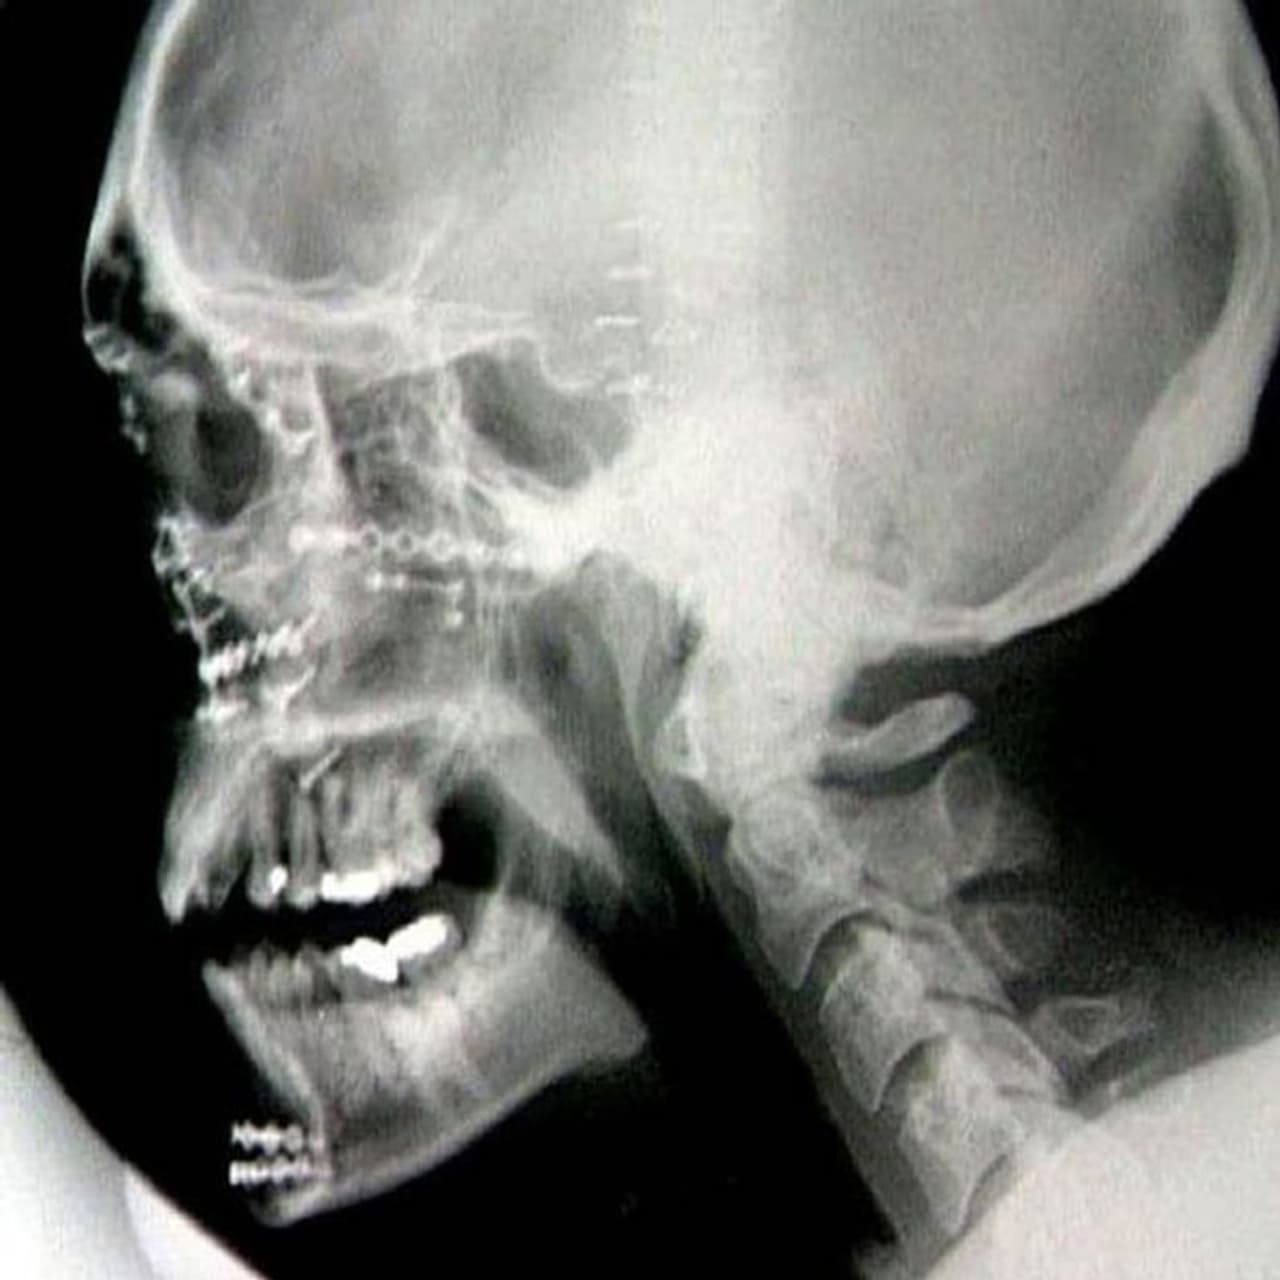

ട്രെവർ ജോൺസിന്റെ എക്സ് റേ

ഇത്രയധികം എല്ലുകൾ മുഖത്ത് ഒടിഞ്ഞിട്ടും വിജയകരമായി മുഖം റീകൺസ്ട്രക്റ്റ് ചെയ്തെടുക്കാൻ സാധിച്ചത് ശരിക്കും അത്ഭുതം തന്നെയാണ് എന്നാണ് ഡോക്ടർമാർ പറയുന്നത്. ഇന്ന് കാണുന്ന ഈ കോലത്തിലേക്ക് ട്രെവറിന്റെ മുഖം പുനർ നിർമ്മിച്ചെടുക്കാൻ ഡോക്ടർമാർക്ക് 150 -ൽ പരം ചെറിയ ചെറിയ ടൈറ്റാനിയം ലോഹക്കഷ്ണങ്ങൾ ഉപയോഗിക്കേണ്ടി വന്നു. പൂർണ്ണമായും ഫോട്ടോ/വിഡിയോഗ്രാഫ് ചെയ്യപ്പെട്ടിട്ടുള്ള ആ പ്രക്രിയ ഇന്ന് ലോകമെമ്പാടുമുള്ള പ്ലാസ്റ്റിക് സർജറി ഇൻസ്റ്റിറ്റ്യൂട്ടുകളിലെ പാഠ്യപദ്ധതിയുടെ ഭാഗം തന്നെയാണ്. അപകടം നടന്ന ശേഷം ആ വണ്ടി കിടക്കുന്ന കിടപ്പു കണ്ടാൽ ആരും തന്നെ, ആ വാഹനത്തിനുള്ളിൽ നിന്ന് ഒരാൾ പോലും ജീവനോടെ പുറത്തു കടന്നിട്ടുണ്ടാകും എന്ന് പറയില്ല.